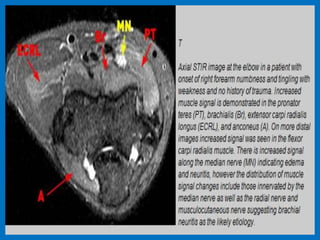

Chronic forearm pain demonstrates subtle increased signal intensity within the pronator teres

and flexor carpi radialis muscles (arrow) compatible with denervation of the median nerve.